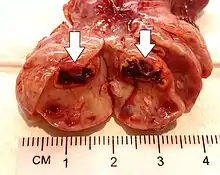

| Corpus luteum cyst | |

A corpus luteum cyst is a type of ovarian cyst which may rupture about the time of menstruation, and take up to three months to disappear entirely. A corpus luteum cyst rarely occurs in women over the age of 50, because eggs are no longer being released after menopause. Corpus luteum cysts may contain blood and other fluids. The physical shape of a corpus luteum cyst may appear as an enlargement of the ovary itself, rather than a distinct mass -like growth on the surface of the ovary.

This type of functional cyst occurs after an egg has been released from a follicle. The follicle then becomes a secretory gland that is known as the corpus luteum. The ruptured follicle begins producing large quantities of estrogen and progesterone in preparation for conception. If a pregnancy doesn't occur, the corpus luteum usually breaks down and disappears. It may, however, fill with fluid or blood, causing the corpus luteum to expand into a cyst, and stay in the ovary. Usually, this cyst is on only one side, and does not produce any symptoms.[1][2]